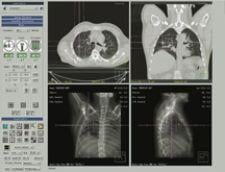

Philips’ exclusive Tumor Localization (Tumor LOC) application allows radiation oncology departments to localize target volumes for radiation therapy planning.

Designed for fast and simple CT tumor volume localization, the application includes exclusive features for viewing Respiratory Correlated CT datasets and analyzing motion of the target and surrounding anatomy.

Previously only available on the Philips Brilliance CT Big Bore console, version 3.5 makes the Tumor LOC application available for purchase on the Extended Brilliance Workspace (EBW) and GEMINI TF PET/CT systems.

All of the best-in-class 4D tools found on the console will now be available on the EBW, reportedly enhancing workflow efficiency and flexibility in the radiotherapy department.